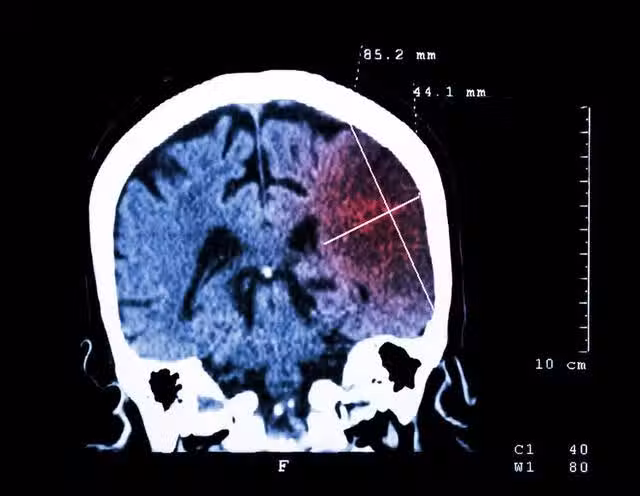

腦梗又名缺血性腦卒中,是一種腦血管疾病。由於腦動脈粥樣硬化、血管內膜損傷等導致腦動脈管腔狹窄,再加上局部血栓導致動脈閉塞加重,從而引發腦組織缺血、壞死、缺氧,就可能引起神經功能障礙。